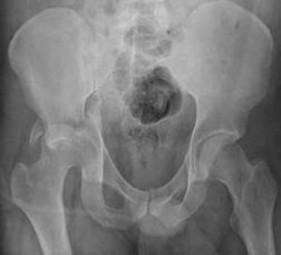

Figure 7Figure 7 is the pelvic radiograph of a 33-year-old man involved in a high-speed automobile crash. Examination reveals a blood pressure of 90/50 mm Hg and a pulse rate of 120/min. Radiographs of the chest and lateral cervical spine are normal. A CT scan of the abdomen does not reveal any intraabdominal bleeding. What is the most appropriate management for the pelvic fracture?